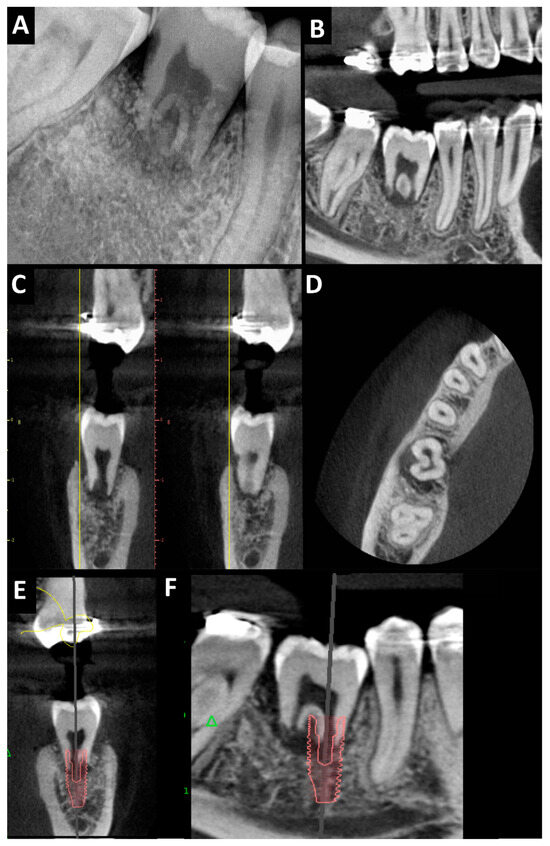

2. Case Presentation